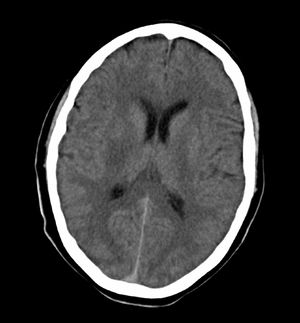

A complementary study (electrocardiogram, echocardiogram, and transcranial and supra-aortic trunk neurosonology) showed no significant changes. The routine CT scan performed 24hours after the IVT revealed an ischaemic lesion affecting the posterior third of the right putamen (Fig. 2). Eight days after admission, the patient was discharged from hospital with left hemiparesis, facial paresis, and dysarthria (NIHSS=8, modified Rankin scale=3).